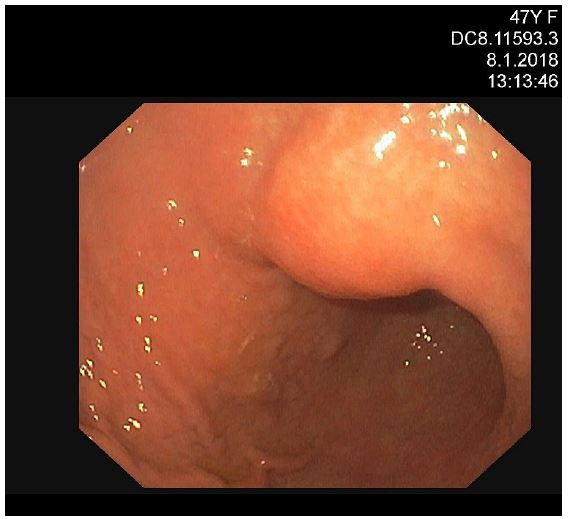

Nevertheless, the patient was assessed by a colorectal Multidisciplinary Team (MDT) at Masaryk Memorial Cancer Institute (MMCI), which decided on adjuvant therapy for the stenotic tumour. Adjuvant chemotherapy on the base of 5 fluorouracil (FU/FA Mayo) was administered. However, this was converted to monotherapy capecitabine due to an allergic skin reaction and neutropenia grade IV. Further therapy was uncomplicated, and close follow-up was recommended. An elevation of tumour marker Carcinoembryonic Antigen (CEA) of 21,8 μg/l was found in October 2017. However, a normal level of the Carbohydrate Antigen (CA) 19-9 of 25.2 ng/ml was noted. Subsequent assessment revealed a left ovarian mass with suspicion of a metastatic process. In November 2017, the patient underwent a gynaecologic evaluation followed by explorative laparotomy at the Department of Gynaecology in the University Hospital Brno. A hysterectomy with bilateral oophorectomy and appendectomy was performed, and malignant ascites was also found. Histological findings showed metastases of moderately differentiated intestinal adenocarcinoma in the left ovary (Figure 1b), identical to the primary transverse colon tumour resected in 2013. KRAS, NRAS and BRAF gene mutations were not detected. The postoperative recovery was uncomplicated, and the patient was referred back to medical oncologists at MMCI. A follow-up Positron Emission Tomography/Computed Tomography (PET/CT) scan was performed in December 2017. It discovered a small metabolically active lesion measuring 12 mm located in the pyloric region closer to the gastric, small curvature (Figure 2). Tumour marker CEA was again slightly elevated (9,4 μg/l) (Figure 3). A gastroduodenoscopy showed prominent gastric walls in the region of the angular notch without mucosal changes. A biopsy was taken, and histologic examination revealed benign atrophic gastritis only (Figure 4).

Figure 4: Gastroduodenoscopy showed prominent submucosal tumour-like elevated lesion in the region of angular notch without mucosal changes.

Gastric metastasis from CRC is rare. In 2001, Oda et al. published a cohort of 347 autopsies of patients with colorectal cancer in which 5.4% had occult gastric metastases, and half of all gastric metastases were mimicking submucosal tumours [19]. The most common primary tumours, which tend to spread to the stomach, were metastases in the lung, breast, malignant melanoma and oesophagus. Typical endoscopic features of gastric metastasis include submucosal and polypoid lesions with central depression [20]. While our case also showed that the endoscopic appearance resembled a submucosal tumour accompanied by central depression and erosion, CRC as a primary site is extremely unlikely, as the biopsy showed chronic gastritis only.